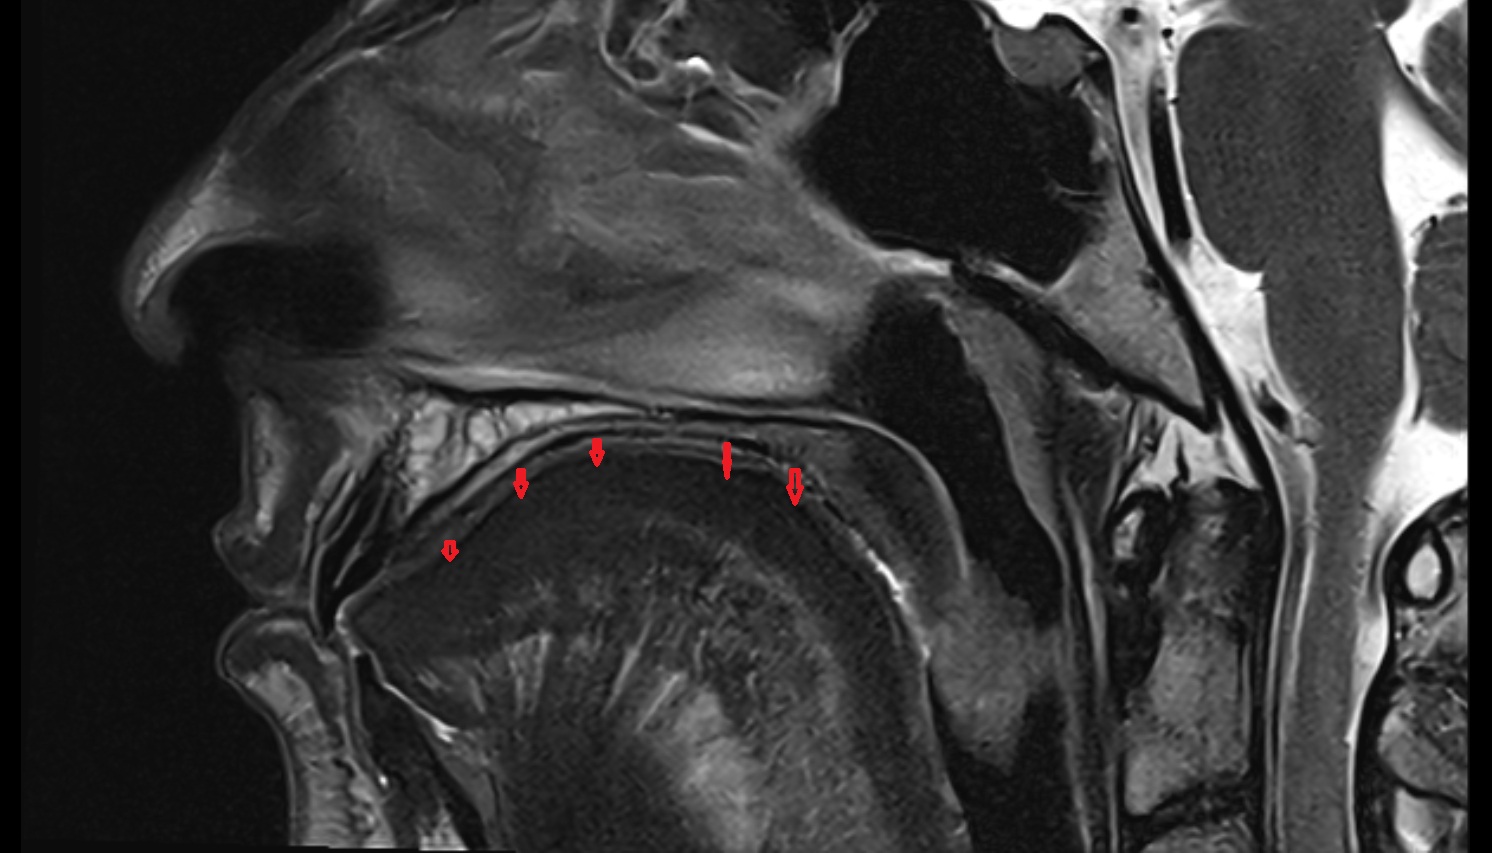

- Temporomandibular joint

- Articular disc of temporomandibular joint

- Articular eminence

- Mandibular condyle

- Mandibular fossa

- Superior head of lateral pterygoid muscle

- Inferior head of lateral pterygoid muscle